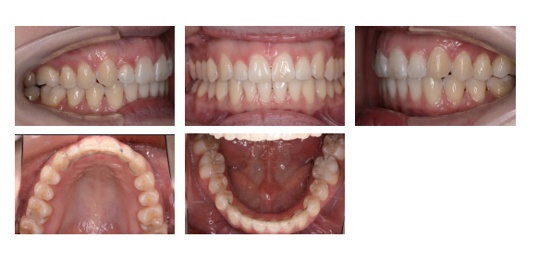

実際に、ここまで改善しています

見た目だけでなく、構造も改善しています

Before / After

横顔は、ここまで変わります

変わるのは、歯並びだけではありません

← スライダーを動かして比較

※ 個人の治療結果であり、全ての方に同様の結果を保証するものではありません。

※歯並びだけでなく、骨格バランスの改善による変化です